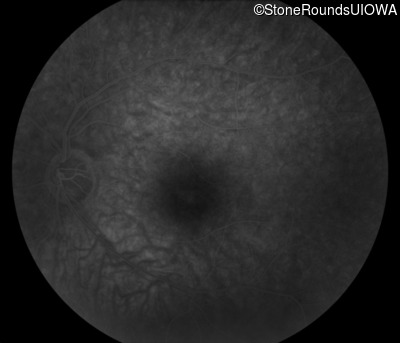

Infrared Fundus Photograph - Left - 20/40

Exemplar